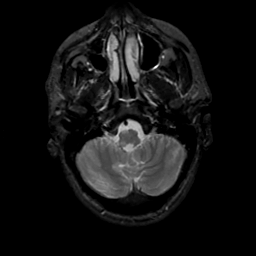

MR Study #16, June 23, 1991 -- Slice #8

[Home][Help][Clinical][Tour 1][Tour 2] Slice 8